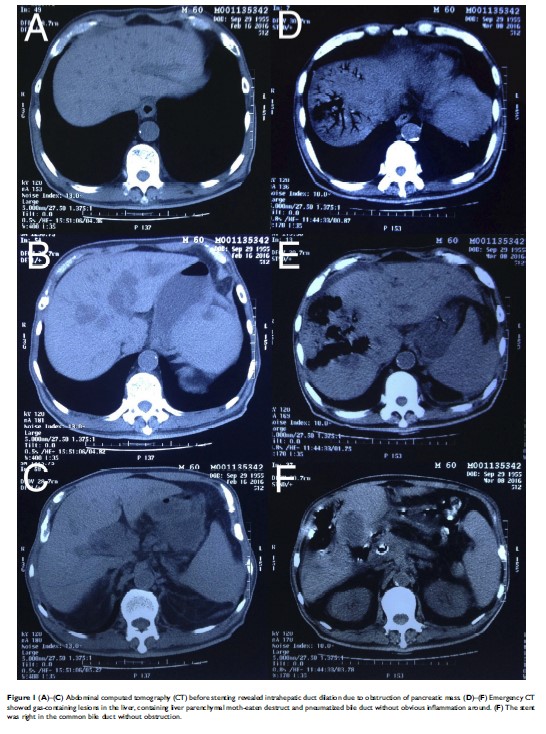

因胰腺癌而行胆管内支架置入术后由产气荚膜梭菌引起的致命性肝感染:一份病例报告